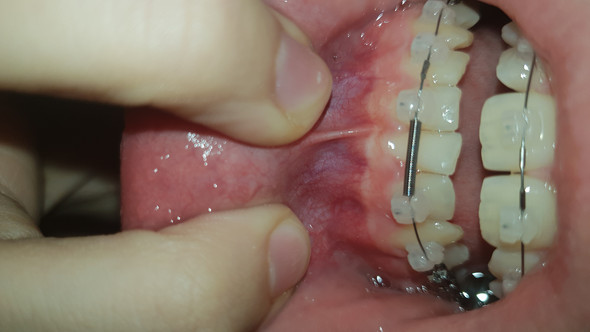

Bei einer Entzündung von Implantaten Periimplantitis zieht sich das erkrankte Zahnfleisch in der initialen Phase der Erkrankung zurück. Das ist beides bei mir nicht der Fall deswegen hängt das eher mit dem Oberlippen-Hebemuskel zusammen oder wie der heißt. Hab mich schon mal ein wenig schlau gemacht und als Ursache waren da ua.

Es ist also nicht nur für Ihre Zahngesundheit. Wieviel Millimeter geht das Zahnfleisch zurück durch Paradontitisbehandlung. Hier kann durch eine gezielte lokale Behandlung mit Antibiotika und eine Reinigung der Zwischenräume schnell dem Zahnfleischschwund am Implantat vorgebeugt werden.